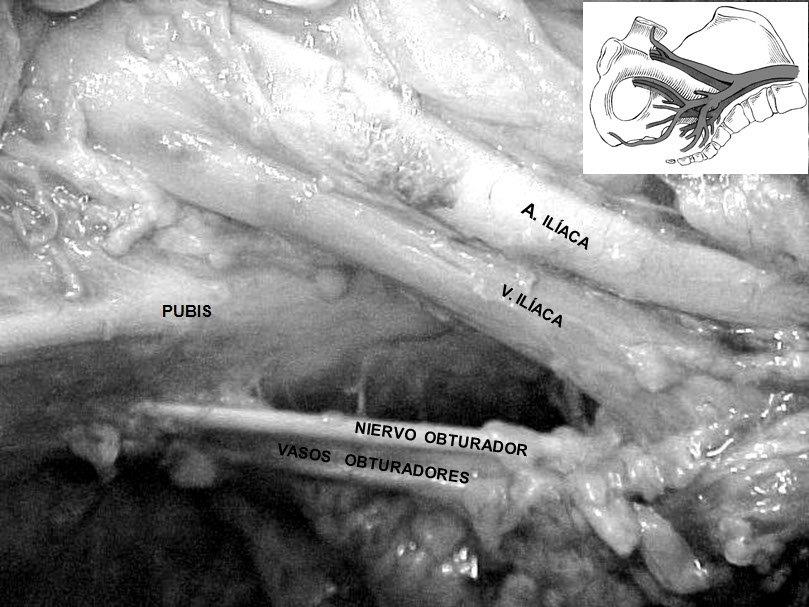

Anastomosis entre vasos ilíacos y obturadores en la región retropúbica: estudio en cadáveres. [Anastomosis among iliac vessels and obturators in the retropubic region: Study in cadavers].